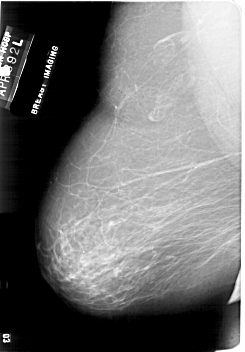

A_1862_1.LEFT_MLO

LEFT_MLO LINES 6676 PIXELS_PER_LINE 4651 BITS_PER_PIXEL 12 RESOLUTION 43.5 NON_OVERLAY